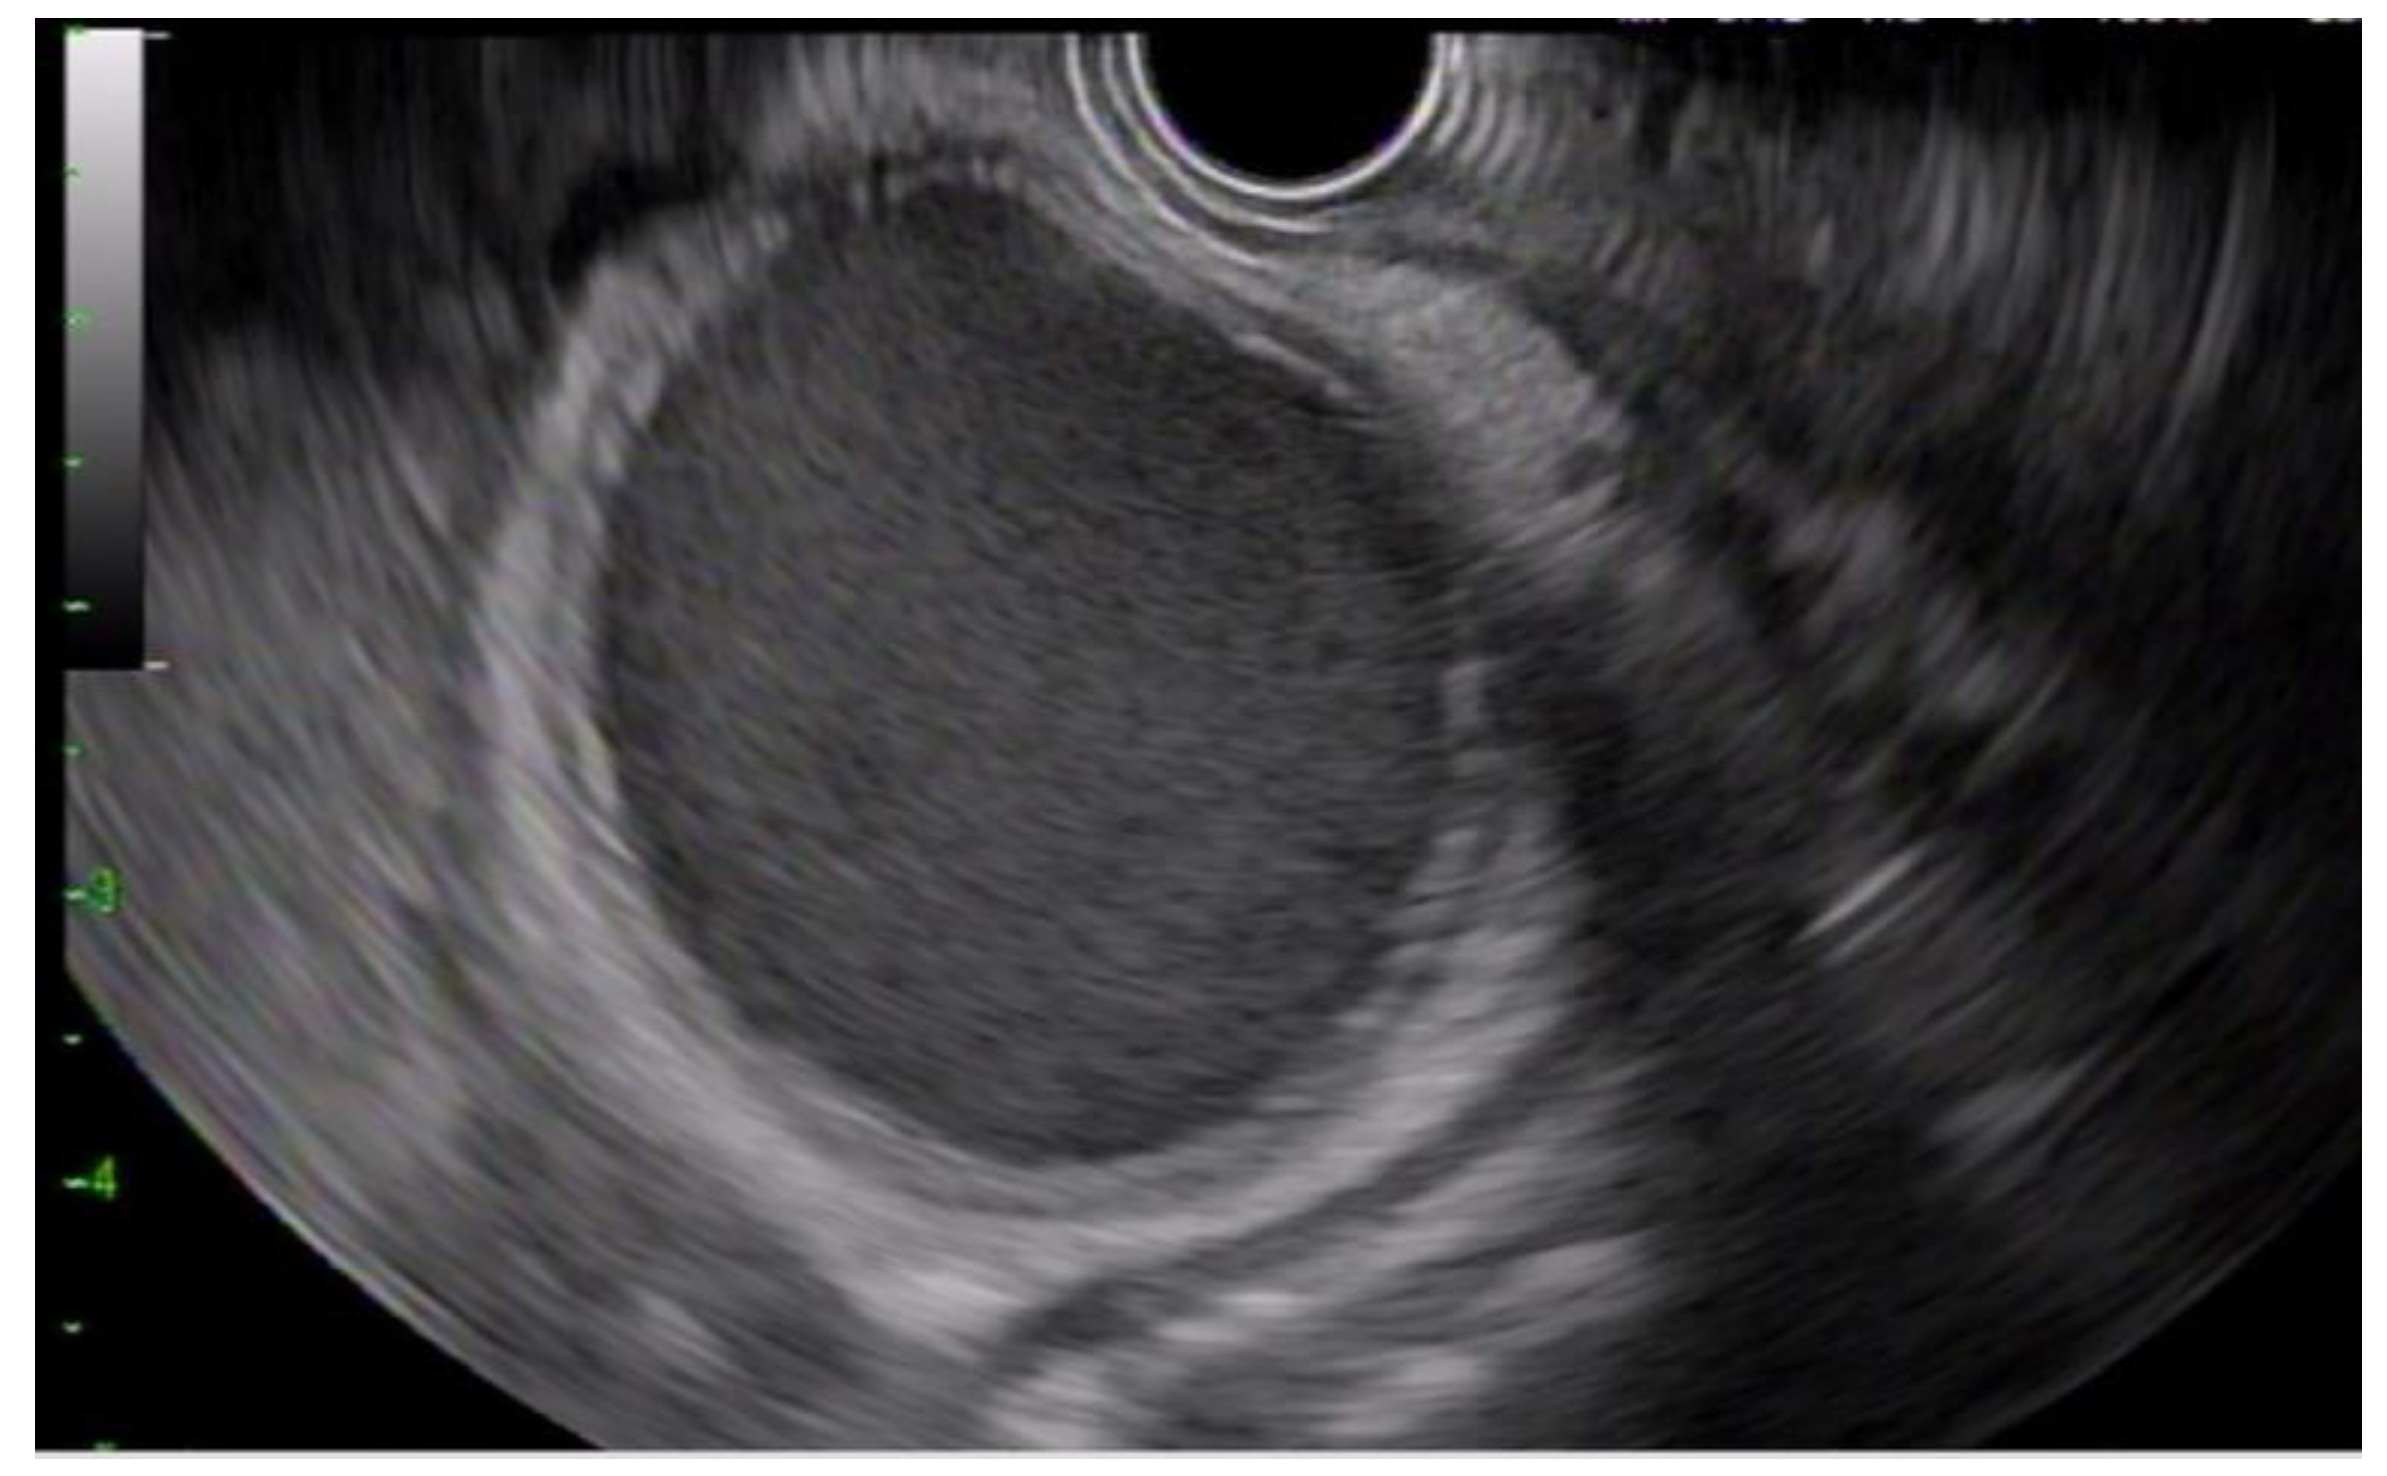

2.4. Procedure Detail